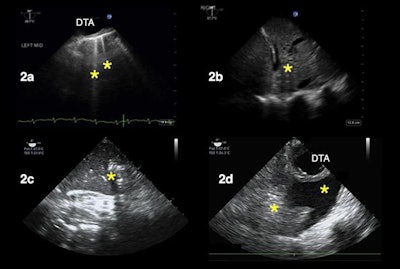

TEE can also be used to image patients' lungs from within their esophagus, also known as transesophageal lung ultrasound (TELUS). This version of lung ultrasound may work particularly well for certain types of patients, such as obese individuals, those with surgical dressing, or those experiencing subcutaneous emphysema, the authors noted.

Other use cases for TEE include evaluating the heart and lungs of patients who must stay in a prone position and those experiencing shock, a finding not uncommon in hospitalized patients with COVID-19, according to the authors.

"We have found that the TEE exam in prone patients has been particularly helpful during the COVID pandemic, given the degree of hypoxemia seen in these patients and the many urgent ECMO evaluations we've had to perform," the authors wrote.